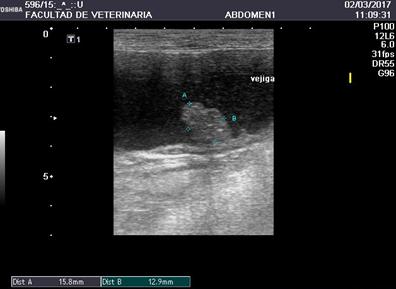

En la ecografía realizada a los 23 meses del diagnóstico se observó vejiga con pared delgada y moderada cantidad de sedimento celular en su contenido. A nivel de la pared derecha, masa hipoecoica irregular de 1,8 x 1,5 cm aprox. En el resto del abdomen no se observaron linfadenopatías ni otras alteraciones (Figura5).

Figura 5: Ecografía a los 23 meses del diagnóstico, donde se observa disminución franca del tamaño de la masa vesical.